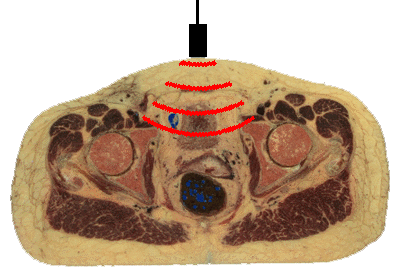

Ultrasound (US) uses high-frequency sound waves for scanning body regions. Ultrasonography is a non-invasive technique that does not use x-rays, so it is safe for any patient. US is commonly utilized for prenatal diagnosis for this reason. To perform US, a transducer generates a focused beam of sound waves that is directed toward the body region to be studied. The sound beam is oriented in a specific plane, such as sagittal (longitudinal) or axial (transverse). The transducer is moved across the external body surface while the image appears on a monitor.

The sound beam srikes body structures that echo (reflect) the sound waves to varying degrees--tissues have different acoustic impedances. The reflected sound waves are detected by the transducer and converted to a series of electrical impulses that is computed to form an image viewed on a screen. Selected views can be captured on film. However, the real advantage of US is the ability to move the transducer in real time and see what is happening. Movement can be detected, such as the beating of a fetal heart. A video can be made of the images to record the movement. Ultrasonographic images are not sharp, but "fuzzy" and require skill in interpretation. A single image is not as useful as a real time exam.

The image displayed on the monitor depends upon the echogenicity of the structures beneath the beam. Fluids are echolucent, so the bladder and the gallbladder appear dark. Solid organs and soft tissues are echogenic. Structures with calcium are very echogenic. A gallstone appears bright with US. Bone is so dense to sound waves that it cannot be evaluated. This puts the brain and spinal cord "off limits" for US examination. US is most suited to study of heart with its valves (which move), gallbladder, vessels (to check for thrombi and flow), and internal genitalia.

Movement can be further enhanced by "doppler" ultrasonography in which flow away from the transducer is converted to a signal that appears blue, while flow toward the transducer appears reddish. This can be useful in recording flow in arteries and veins.